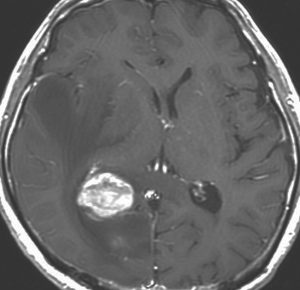

MRI検査で,はっきりわかります。MRI造影剤を入れると均一または斑らに増強(真っ白になる)されて(左側),周囲には脳の腫れ(脳浮腫)がみられます(右側)。できやすい場所は側脳室の周囲・大脳脳基底核・小脳・脳幹部など脳の深いところ(深部白質)です。脳の中に2個以上のリンパ腫が同時にできる多発例というのもしばしばあります

若い患者さんのリンパ腫です。左が診断時MRIで,黄色の矢印でみれる3ヶ所に同時にリンパ腫が発生しています。定位生検術後にすぐにMTX化学療法を3コースしたら,真ん中の画像になりました。ほとんど消失しているのですが,矢印の先にぼーっと少し残っているのでCR(消失)とはいいません。化学療法を終えた後に全脳照射30グレイをしたら右の画像になり治りました。これは順調な治療経過の例です。